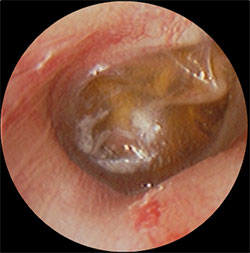

・鼓膜の内側に褐色の液体の貯留を認める

などの症状がでてきます。

・上記の滲出性中耳炎の鼓膜に小さな切開をいれ、内部の液体を吸引し、鼓膜チューブを挿入

・左図の処置後から1週間後、鼓膜内側には液体は溜まっておらず、正常の鼓膜の色である